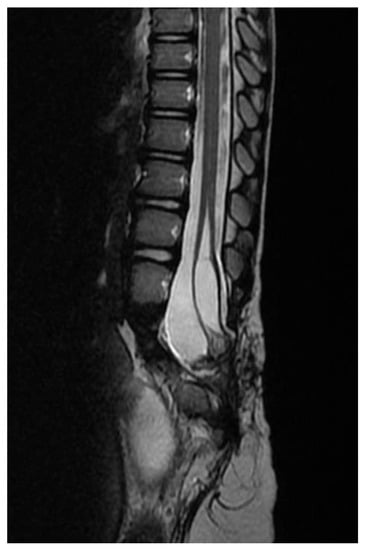

Split Notochord Syndrome with Spinal Column Duplication and Spinal Cord Lipoma: A Case Report

2. Clinical Presentation